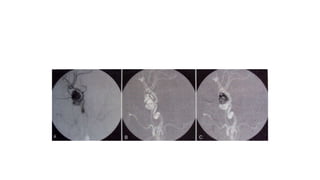

ROADMAPPING

• Roadmapping is a special application of DSA.

• A mask image is acquired and stored and CM is injected and

subtraction images are acquired as in DSA (A).

• As the catheter is fluoroscopically advanced, the image is formed by

subtraction form the second mask (B).

• Final DSA image shows completer vasculature tree with good contrast

(C).

• This image is inverted and used as the mask for additional DSA images.